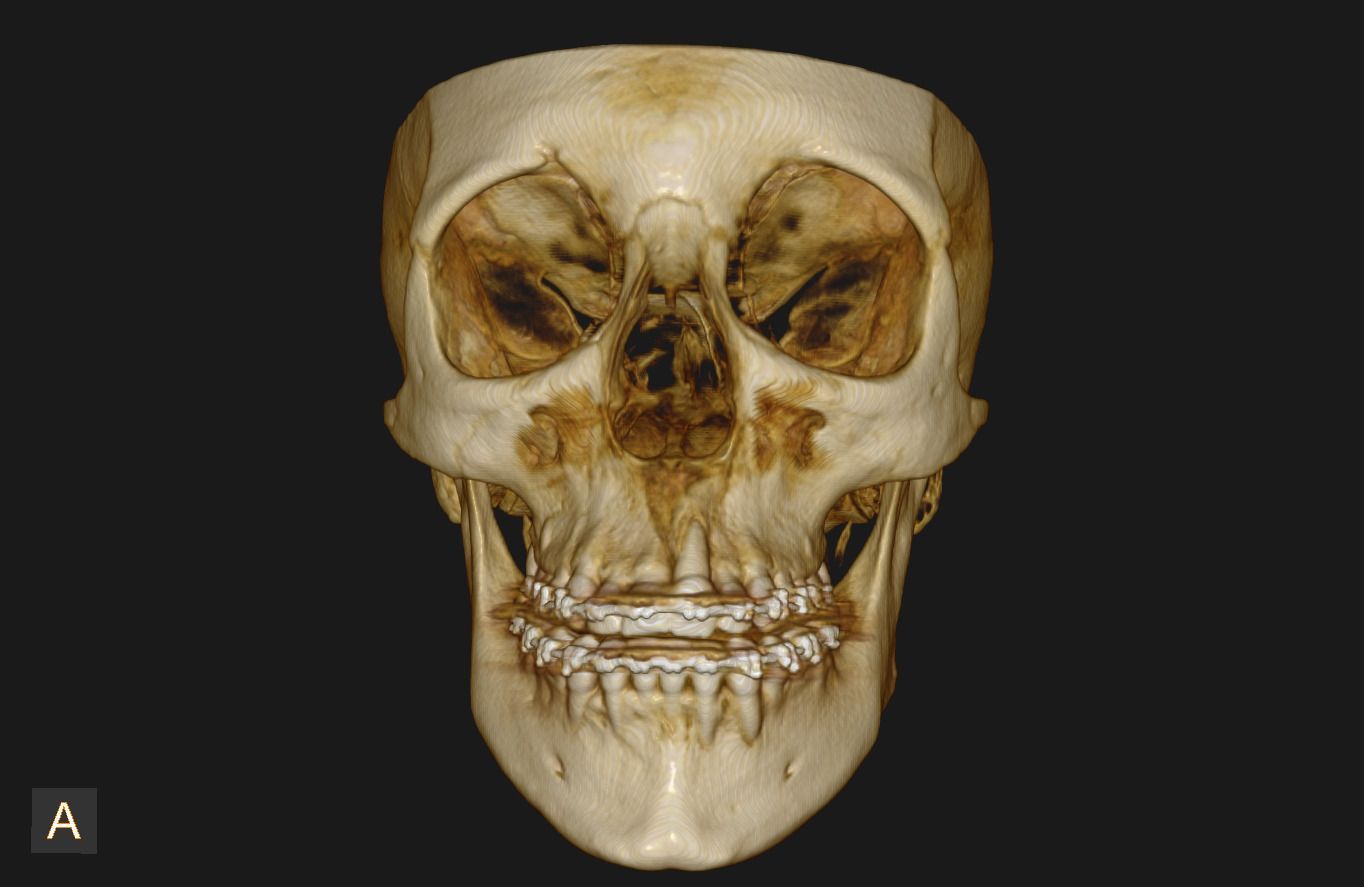

Uno de nuestros principales servicios es la adquisición de imágenes dentales 2D y 3D, fundamentales para un diagnóstico preciso y una planificación adecuada de tratamientos dentales.

Contamos con tecnología avanzada que nos permite obtener imágenes claras y detalladas de la boca y los tejidos circundantes, lo que es crucial para evaluar la salud dental y detectar posibles problemas.